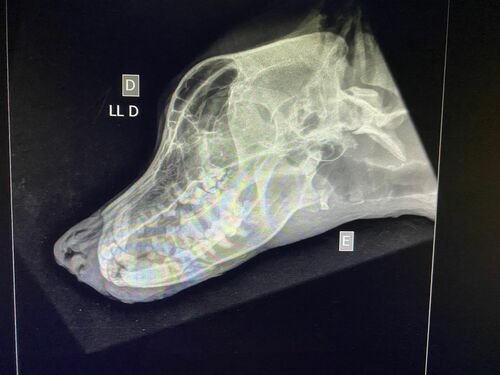

Infelizmente no dia 15/04 ele foi vítima de um atropelamento, como consequência teve fratura no maxilar e na patinha, e também está com processo inflamatório no pulmão!Os tutores não tem condições para arcar com todos os gastos, porque além disso tudo, o dono/companheiro do Campeão é portador do Autismo, e ele precisa URGENTEMENTE do seu melhor amigo em casa novamente!A cirurgia das fraturas está no valor de $3000. Além disso ele precisa de internação e controle com medicação no pós cirurgico.